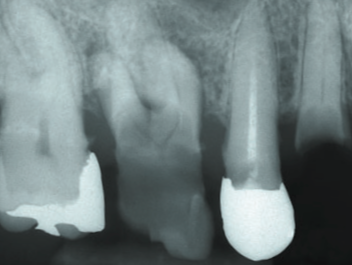

虫歯菌(ミュータンス菌)によりエナメル質が溶け神経まで虫歯菌が進行すると神経が炎症を起こし痛みを伴います。症状としては、冷たい物や温かい物がしみる、何もしなくても痛いと感じることがあります(この症状があったからと言って必ず神経を取るわけではありません)。神経まで虫歯が進行しているにもかかわらず治療せずに放置すると、根の先に膿がたまり根の先の顎の骨が溶けることがあります。

全体が、むし歯に侵されています 歯の根の先に膿がたまったり、歯のまわりにも 病気の影響がおよび、歯を残すのがむずかしくなります

歯が虫歯菌により溶けて形が残っていない状態です

ここまでくると歯の痛みはありませんが、歯茎が腫れた痛みや根の先が細菌感染し膿がたまり骨の内部で顎の骨が溶けることがあります。骨が細菌感染し急激に痛みを伴うこともあり虫歯で神経が感染した場合よりも痛みが強いことがあります。

歯茎の中まで虫歯が進行し、歯質が残っていないため、例え痛みがなくても治療できるほど歯が残っていないため保存不可能となり、ほとんどの場合は抜歯となります